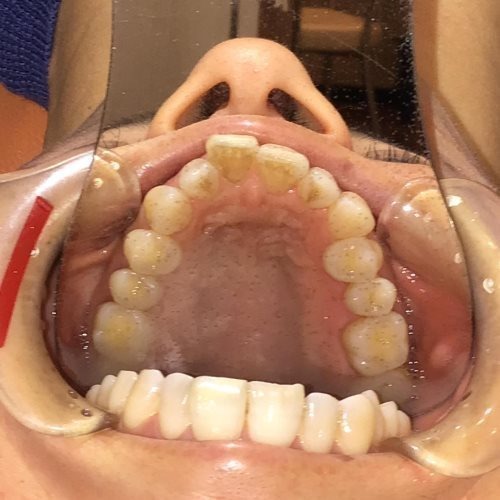

上顎